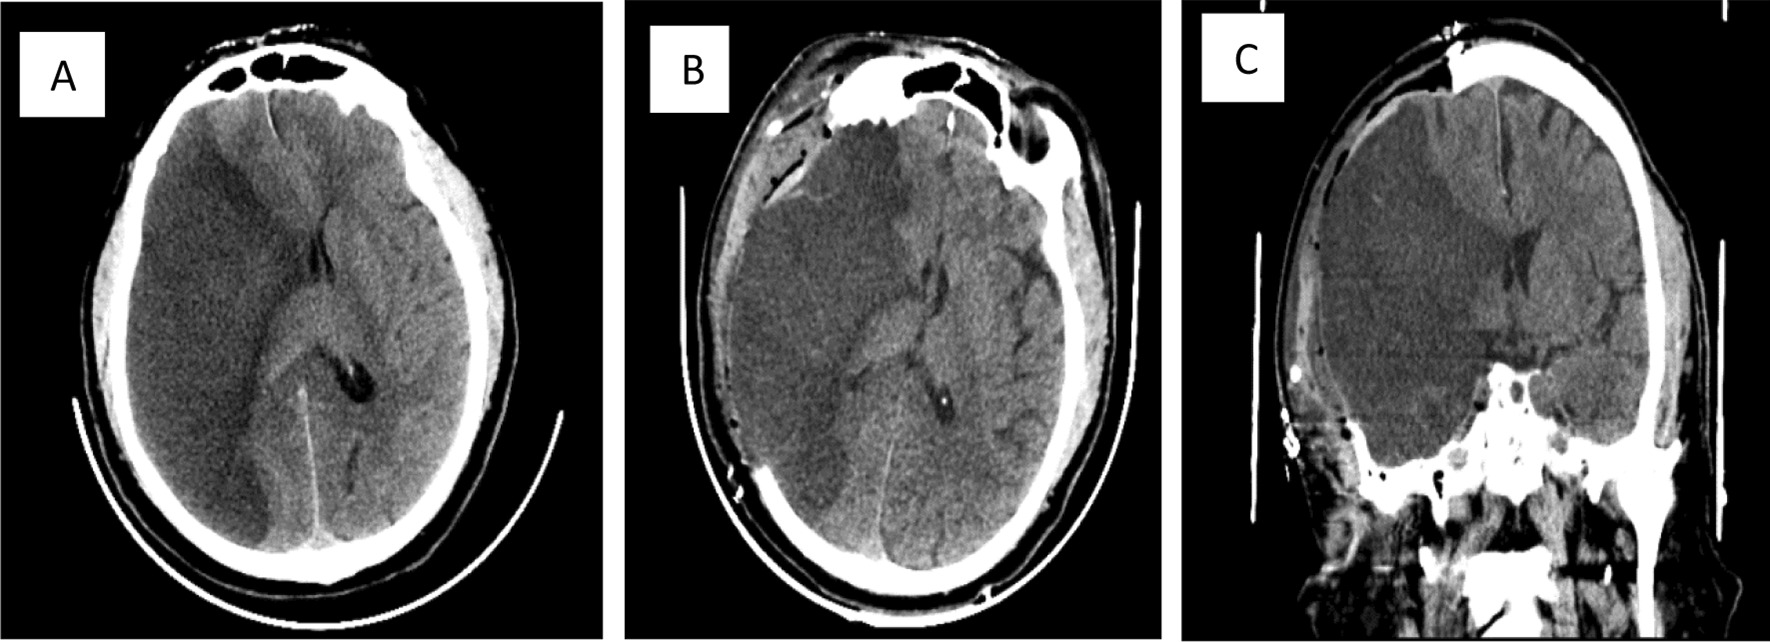

On examination, the patient was conscious but confused. He had left facial weakness, gaze deviation to the right side, left homonymous hemianopsia, dense left hemiplegia, and left sided hemineglect, so the stroke code was announced. Both a computed tomography (CT) scan and a CT angiogram were performed upon admission. The CT scan of the brain showed an ischemic stroke of the right temporal lobe surrounded by diffuse brain edema causing mass effect (Fig. 1). The CT angiogram revealed nonopacification of the right internal carotid artery near its origin with extension cranially to involve the majority of the cervical portion in addition to the petrous, cavernous, and supraclinoid aspects. In addition, there was nonopacification of the right middle cerebral artery (MCA) branches, which was likely due to thrombus formation. Additionally, the brain MRI findings are illustrated in Fig. 2.

Fig.1.

A Extensive hypodense lesion on the right temporal area on the axial noncontrast brain CT before thrombectomy. B Large hypodense lesion of the right temporal area after craniotomy was done on the axial noncontrast brain CT. C Coronal brain largely affected by hypodense lesion on the right temporal area